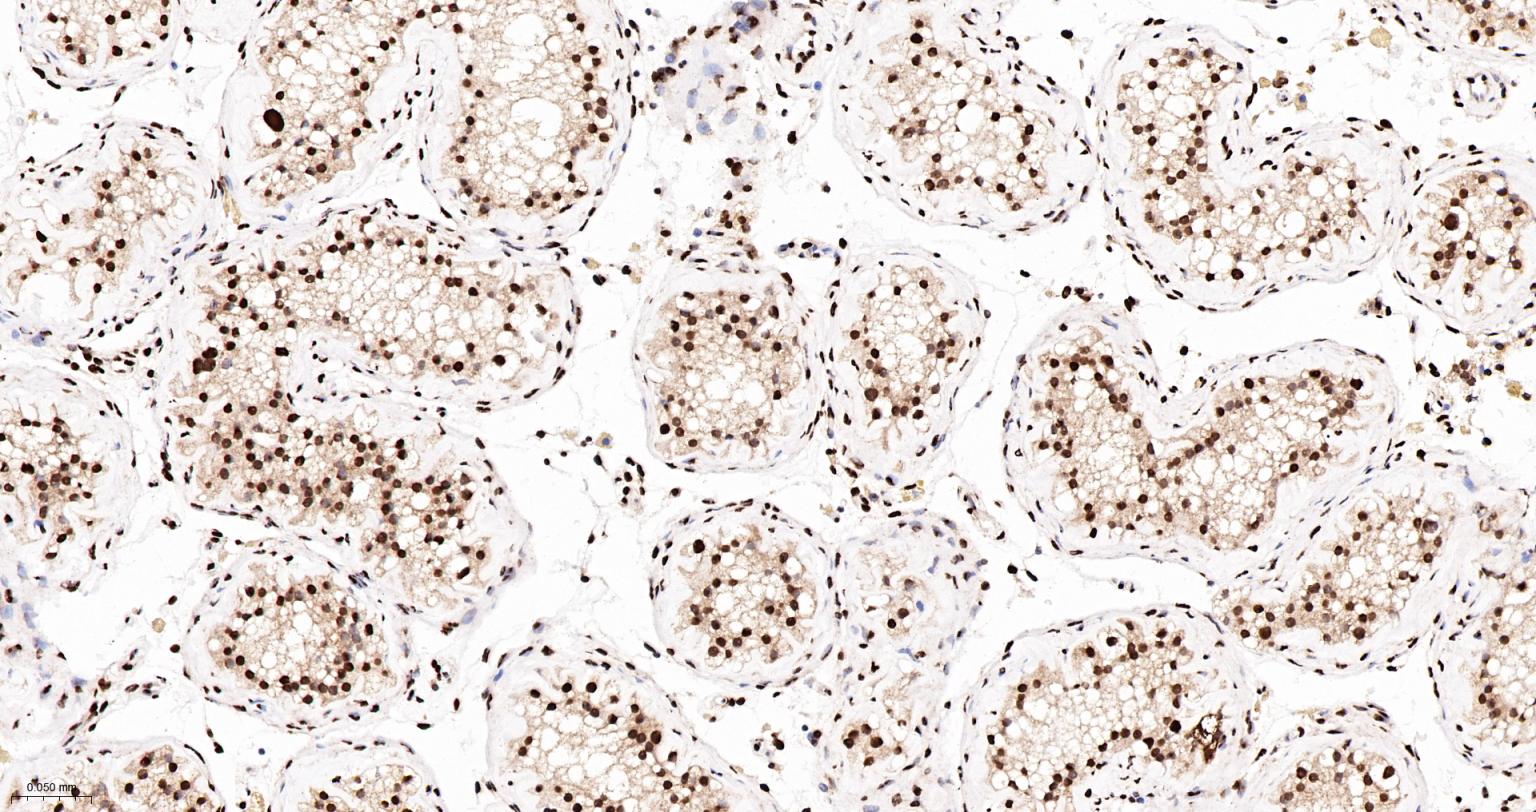

Paraformaldehyde-fixed, paraffin embedded Human Testicles; Antigen retrieval by boiling in sodium citrate buffer (pH6.0) for 15 min; The section was incubated with hnRNP K Monoclonal Antibody, Unconjugated (bsm-61246R) at 1:200 overnight at 4°C, followed by conjugation to the bs-0295G-HRP and DAB (C-0010) staining.